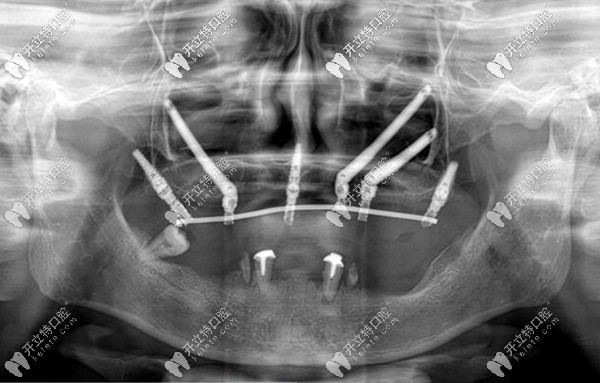

穿顴骨種植技術(shù),也被稱為“無土栽培”技術(shù)。杭州美奧口腔王明來給大家詳細(xì)講解什么是穿顴種植,以及穿顴骨種植的利弊有哪些。